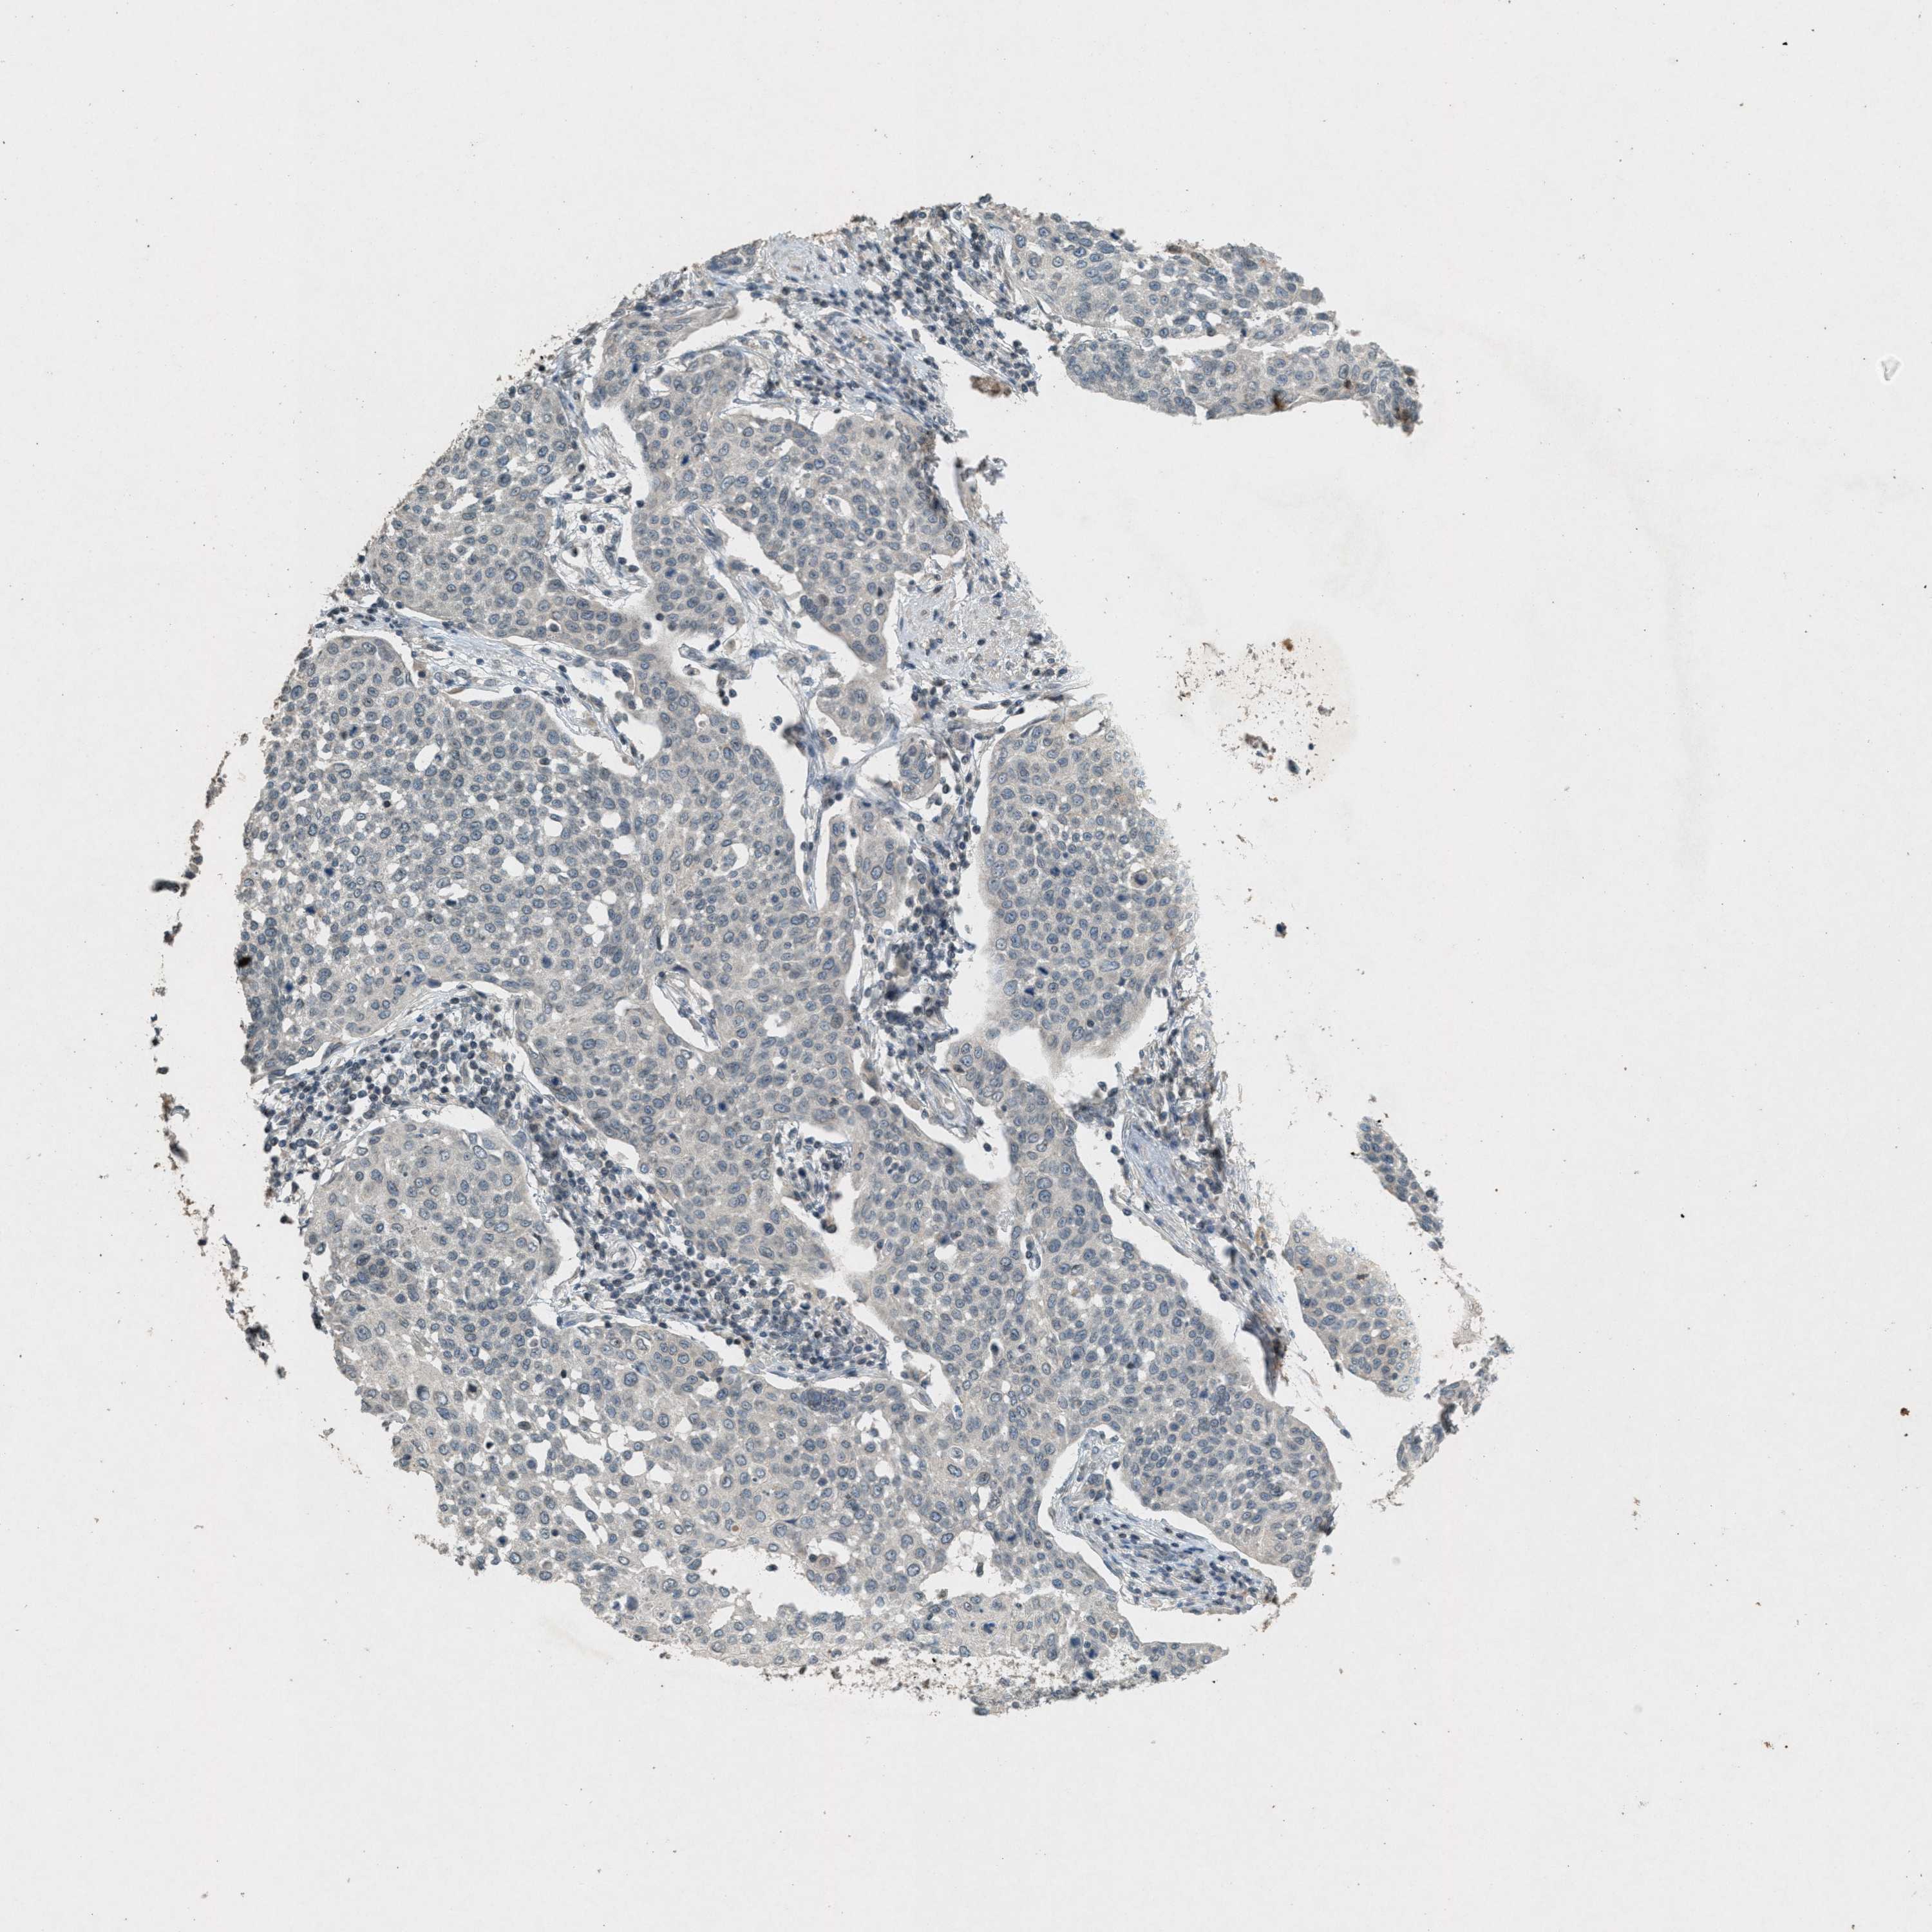

CERVICAL CANCER - Protein expressioni

A mouse-over function shows sample information and annotation data. Click on an image to view it in a full screen mode. Samples can be filtered based on level of antibody staining by selecting one or several of the following categories: high, medium, low and not detected. The assay and annotation is described here.

Note that samples used for immunohistochemistry by the Human Protein Atlas do not correspond to samples in the TCGA dataset.

Antibody stainingi

Antibody staining in the annotated cell types in the current human tissue is reported as not detected, low, medium, or high, based on conventional immunohistochemistry profiling in selected tissues. This score is based on the combination of the staining intensity and fraction of stained cells.

Each image is clickable and will lead to virtual microscopy that enables deeper exploration of all samples and also displays staining intensity scores, fraction scores and subcellular localization as well as patient and tissue information for each sample.

Antibody HPA017283

Staining

High

Medium

Low

Not detected

Intensity

Strong

Moderate

Weak

Negative

Quantity

>75%

75%-25%

<25%

None

Location

Nuclear

Cytoplasmic/membranous

Cytoplasmic/membranous,nuclear

Squamous cell carcinoma, NOS

Adenocarcinoma, NOS